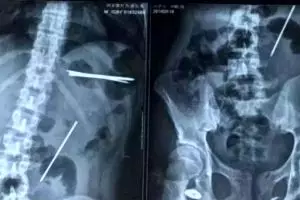

8 Paku sepanjang 15 cm bersarang dan menusuk perut pria ini, duh!

02 / 06 / 2016 16:37